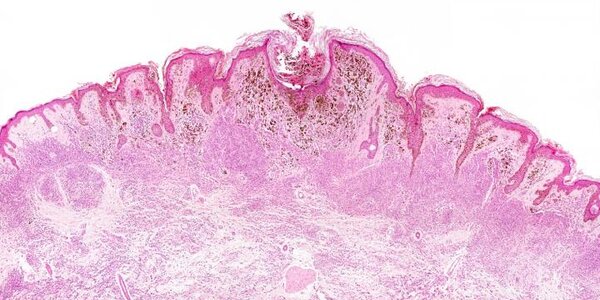

Dermatopathologists, skin cancer specialists, may be ordering additional tests or second opinions out of caution but they may also be thinking about checking off boxes to prevent malpractice lawsuits. In the United States, with the existing "Wild Wild West" of litigation due to blocks of tort reform, it is routine for lawyers to sue doctors, hospitals, and insurance companies. Using claims that they "hold corporations accountable", malpractice lawsuits are so routine it's rare not to have one: 74 percent of obstetricians and gynecologists will face malpractice claims by age 45, which means…